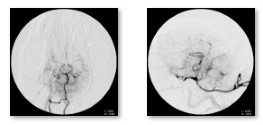

주요 프로그램으로는 △뇌혈관 인터벤션과 혈관조영 실습 △뇌종양 수술 최신 술기 △자동조절 밸브 VP 션트 수술 △뇌혈관 수술 전략 △오마야 리저버 삽입 수술 등을 다뤘는데, 특히 웨스턴동물의료센터 뇌종양 환자에 혈관 색전술을 적용한 뒤 종양 절제술로 이어지는 시뮬레이션을 통해 수술 시간 단축과 출혈 감소, 환자 안전성 향상 가능성을 확인해 관심을 집중시켰다.